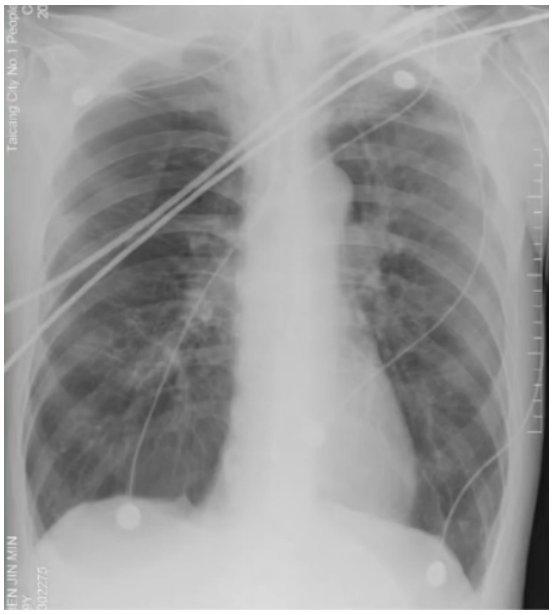

床旁支气管镜:隆突锐利,左右各叶支气管可见少量黏稠白色分泌物,予充分吸引,未见明显痰栓,各叶段予生理盐水肺泡灌洗,回收灌洗液(BALF),送检微生物培养。D-二聚体0.98 mg/L(胃内容物隐血阳性,预防性抗凝暂未实施,物理预防VTE)。考虑出现人机不协调可能是气道痉挛所致。调整呼吸机参数,更换为容量控制+压力支持模式,设定VT 为350 ml;加用阿曲库铵肌松;气道雾化治疗频率更换为q4h;甲泼尼龙剂量调整为40 mg q12h。调整后气道峰压下降至22 cmH2O。复查血气分析:pH 7.343,PaCO2 64.5 mmHg,PaO2 152 mmHg,氧合指数381 mmHg,乳酸1.5 mmol/L。患者呼气相延长好转,气促症状改善。2024年1月23日20:07,患者入院46 h,气促较前加重,哮鸣音明显,RASS评分-1分。复查血气分析:pH 7.206,PaCO2 104 mmHg,PaO2 59 mmHg,HCO3- 41.4 mmol/L,乳酸0.8 mmol/L。复查胸片:未见右侧新发气胸,左侧气胸未见进一步吸收,炎症不明显(图3)。予加深镇静镇痛。调整呼吸机参数为SIMV+PSV。1月23日22:04血气分析:pH 7.276,PaCO2 86.8 mmHg,PaO2 71.7 mmHg,HCO3- 40.4 mmol/L,乳酸1.3 mmol/L。1月24日09:34血气分析:pH 7.335,PaCO2 80 mmHg,PaO2 67.7 mmHg,HCO3- 40.1 mmol/L,乳酸1.3 mmol/L。(1)患者二氧化碳潴留反复加重的原因是什么?气道痉挛缓解困难的原因是什么?(2)并发气胸加重?——复查胸片可以排除这种可能。(3)并发肺栓塞?——D-二聚体基本正常,临床表现也无明显证据。1月24日BALF培养结果提示为烟曲霉。是否是致病菌?该患者危险因素符合:①慢性病基础(慢阻肺);②糖皮质激素应用史;③广谱抗生素应用史。不符合之处:①体温正常;②炎症指标正常;③胸部影像学未见新发感染征象;④外周血G试验/GM试验正常。1月24日加用伏立康唑片剂0.2 g q12h鼻饲,复查胃内容物隐血阴性,VTE评分5分(高危),根据体重调整剂量后加用依诺肝素3000 U预防性抗凝治疗。甲泼尼龙减量至40 mg qd,雾化减至q12h。继续有创呼吸机辅助通气,动态调整呼吸机参数,镇静镇痛,肌松。完善lgE、过敏原检测;动态复查胸片、血气分析、炎症指标。检查结果回示:IgE 37 lU/ml;吸入物+食入物过敏原阴性。1月26日复查血常规+hs-CRP:WBC 6.4×109/L,NEU% 92.0%,EOS% 0.0%,Hb 124 g/L,PLT 201×109/L,hs-CRP 9.24 mg/L。呼吸机参数:SIMV+PSV, PCV/PSV 20 cmH2O, PEEP 10 cmH2O, VT 200~500 ml。1月25日血气分析:pH 7.402,PaCO2 70.1 mmHg,PaO2 94.4 mmHg,氧合指数270 mmHg,乳酸1.1 mmol/L。1月26日血气分析:pH 7.431,PaCO2 67.7 mmHg,PaO2 80.5 mmHg,氧合指数230 mmHg,乳酸1.4 mmol/L。1月27日血气分析:pH 7.462,PaCO2 60.8 mmHg,PaO2 88.2 mmHg,氧合指数252 mmHg,乳酸1.6 mmol/L。1月27日复查胸片:与1月24日胸片对比,气胸未进一步加重,亦未见新发感染病灶(图4)。患者气道痉挛仍然存在,1月27日试停肌松后气道痉挛加重,人机不协调,脱机困难,1月29日出现发热(图5),气道内分泌物未见增多。抗感染药物已经覆盖了烟曲霉,患者为何出现发热症状——口服伏立康唑血药浓度不足?合并其他微生物感染?出现脓毒血症?寻找依据:查伏立康唑血药浓度为5.26 μg/ml(正常范围)。1月29日复查血常规:WBC 6.7×109/L,NEU% 89.3%,EOS% 0.0%,Hb 127 g/L,PLT 260×109/L,hs-CRP 3.66 mg/L。PCT、IL-6均正常,完善血培养【5~7天,等待结果】。经验性加强抗感染,停用哌拉西林他唑巴坦,更换为美罗培南。BALF送检NGS进一步明确致病菌。1月31日复查胸片:没有明显的新发感染迹象(图6)。送检BALF NGS 1天后结果回报:烟曲霉(序列数2272),乙型流感病毒(序列数47)。伏立康唑改为针剂0.2 g q12h,联合卡泊芬净50 mg qd(首剂70 mg),联合两性霉素B脂质体50 mg biw雾化;加用玛巴洛沙韦抗病毒。患者气道痉挛明显,气胸风险大,床边备胸膜切开包。复查血常规+hs-CRP:WBC 7.8×109/L,NEU% 86.6%,Hb 130 g/L,PLT 198×109/L,hs-CRP 1.0 mg/L。血培养回报阴性(双瓶双侧)【脓毒血症依据不足】。经过上述治疗,患者体温较前下降,支气管镜下气道分泌物较前减少,气道痉挛部分缓解,呼吸机参数改善,试停肌松。1月31日血气分析:pH 7.423,PaCO2 59.9 mmHg,PaO2 75 mmHg。2月1日血气分析:pH 7.420,PaCO2 58.6 mmHg,PaO2 81.2 mmHg。2月4日患者再次出现发热,体温最高38.1℃,气道痉挛加重,血气分析提示二氧化碳潴留加重,PaCO2 71.6 mmHg。复查炎症指标:WBC 12.2×109/L,NEU% 93.2%,hs-CRP 32.97 mg/L,PCT 0.068 ng/ml,IL-6 19.8 pg/ml。复查胸片提示两肺炎症改变,右肺下野团片影(图7)。复查BALF细菌培养:纹带棒状杆菌>103CFU/ml。真菌培养:无真菌生长。复测伏立康唑血药浓度3.03 μg/ml。纹带棒状杆菌是定植,还是致病?2月4日复查胸部CT:与入院时CT相比,出现两下肺斑片渗出影(图8)。考虑患者合并细菌感染。